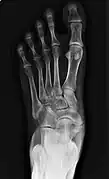

Radiological images

The Geist classification divides the accessory navicular bones into three types.[3]

• Type 1: An os tibiale externum is a 2–3 mm sesamoid bone in the distal posterior tibialis tendon. Usually asymptomatic.

• Type 2: Triangular or heart-shaped ossicle measuring up to 12 mm, which represents a secondary ossification center connected to the navicular tuberosity by a 1–2 mm layer of fibrocartilage or hyaline cartilage. Portions of the posterior tibialis tendon sometimes insert onto the accessory ossicle, which can cause dysfunction, and therefore, symptoms.

• Type 3: A cornuate navicular bone represents an enlarged navicular tuberosity, which may represent a fused Type 2 accessory bone. Occasionally symptomatic due to bunion formation.